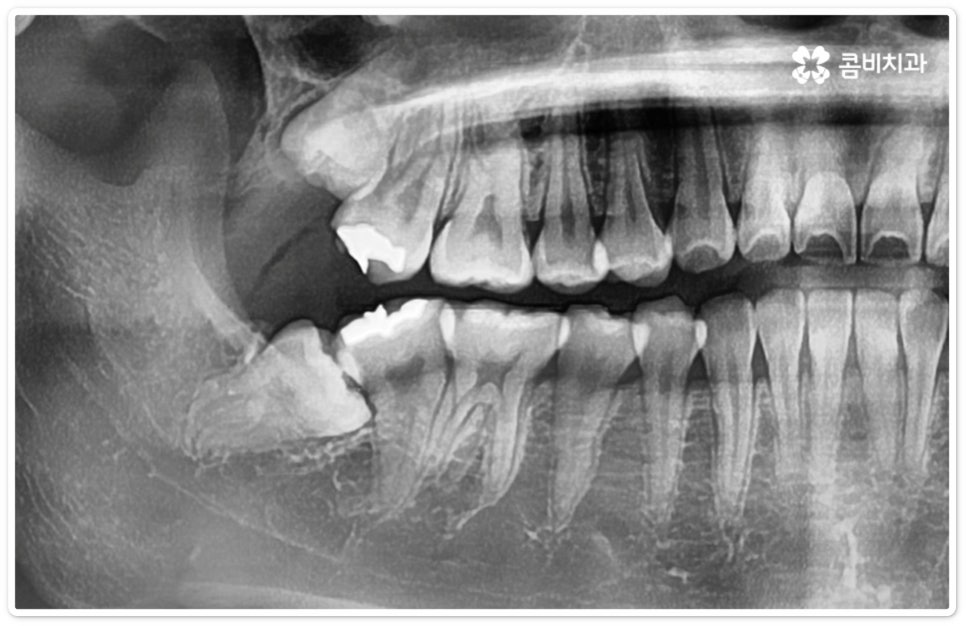

사랑니의 개수, 위치, 각도나 뿌리의 형태, 매복 깊이 등은 사람마다 다른데 그 중에서 특히 완전히 매복된 상태로 비스듬히 누운 채 자리잡은 아래 사랑니의 경우 턱을 가로지르는 하치조 신경과 가깝기 때문에 누운사랑니발치 시 신중을 기하지 않으면 혹시 모를 부작용인 감각 이상을 초래할 수 있으므로 뛰어난 해부학적 지식과 풍부한 임상 경험, 세심한 기술력을 가지고 있는 숙련된 의료진에게 치료를 받으시길 권유드리고 있어요. 혹시라도 신경 손상이 발생하게 되면 입술이나 턱이 마취된 듯 침이 흘러도 감각이 없거나 양치질을 할 때 물이 입술밖으로 세어나가는 상태가 유발될 수 있으니 조심해야 할 거예요.

매복 형태의 사랑니는 잇몸을 절개하고 발치해야 하며, 특히 깊숙하게 누운사랑니발치 시에는 신경을 건드리지 않도록 사랑니를 조각내어 조심해서 빼내야 할 뿐 아니라 환자분들의 상태에 따라 잇몸뼈를 조금씩 삭제해야 할 수도 있기 때문에 이러한 고난도 시술에는 주변 조직의 손상을 최소화하고 혹시 모를 부작용의 위험을 줄이며 출혈 및 통증이 커지지 않도록 하기 위해서 시술자의 높은 숙련도가 더욱 요구된다고 할 수 있어요. 또한 매복된 사랑니의 각도, 뿌리 형태, 인접 치아와의 관계, 신경 위치 등을 정확하게 파악하고 체계적인 맞춤 계획을 세워 무리하지 않게 사랑니 발치 수술을 진행하기 위해서 정밀 진단이 가능한 3D CT 장비가 있는 치과에서 꼼꼼한 검사부터 받아보는 것이 중요할 거예요.